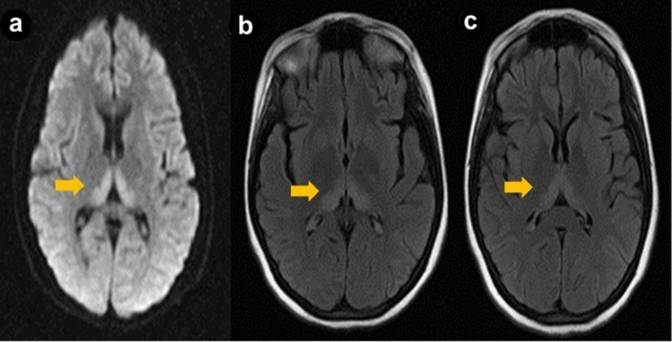

After 15 days of a favorable clinical course, and after the acute episode was resolved, the patient was referred to the surgery department for a laparoscopic pancreatic necrosectomy and cholecystectomy. These procedures were uneventful, and the patient was admitted to the surgical ward for recovery. At this point, the neurological exam was normal, and the patient was afebrile and hemodynamically stable. The patient was again referred to the internal medicine department at the 8th post-operative day because of mental status changes, including drowsiness, confusion and dizziness. At interrogation, the patient complained of severe headache and diplopia. At neurological examination, she had a horizontal nystagmus, VI cranial nerve palsy, signs of cerebellar dysfunction, short term memory impairment, and lethargy. Deep tendon reflexes were increased in lower limbs. General muscle weakness (4/5) was also found. Her blood glucose was normal; she had low hemoglobin (10.6 g/dL; reference range: 12.2-18.1 g/dL), no signs of meningeal irritation and a normal spinal fluid analysis. Antinuclear antibodies were negative and thyroid function tests normal. Because of the prolonged fasting, Wernicke encephalopathy was suspected. A contrasted brain MRI was performed that showed hyperintensive signals in periventricular areas, medial thalamus, and mammillary bodies, findings consistent with the diagnosis of Wernicke encephalopathy (Figure 1). An electroencephalography was performed.

Figure 1. Brain magnetic resonance imaging (fast spin echo). a. Diffusion. b., c. T2 flair (arrows): bilateral and symmetrical hyperintense lesions in pulvinar and dorsomedial thalami. |